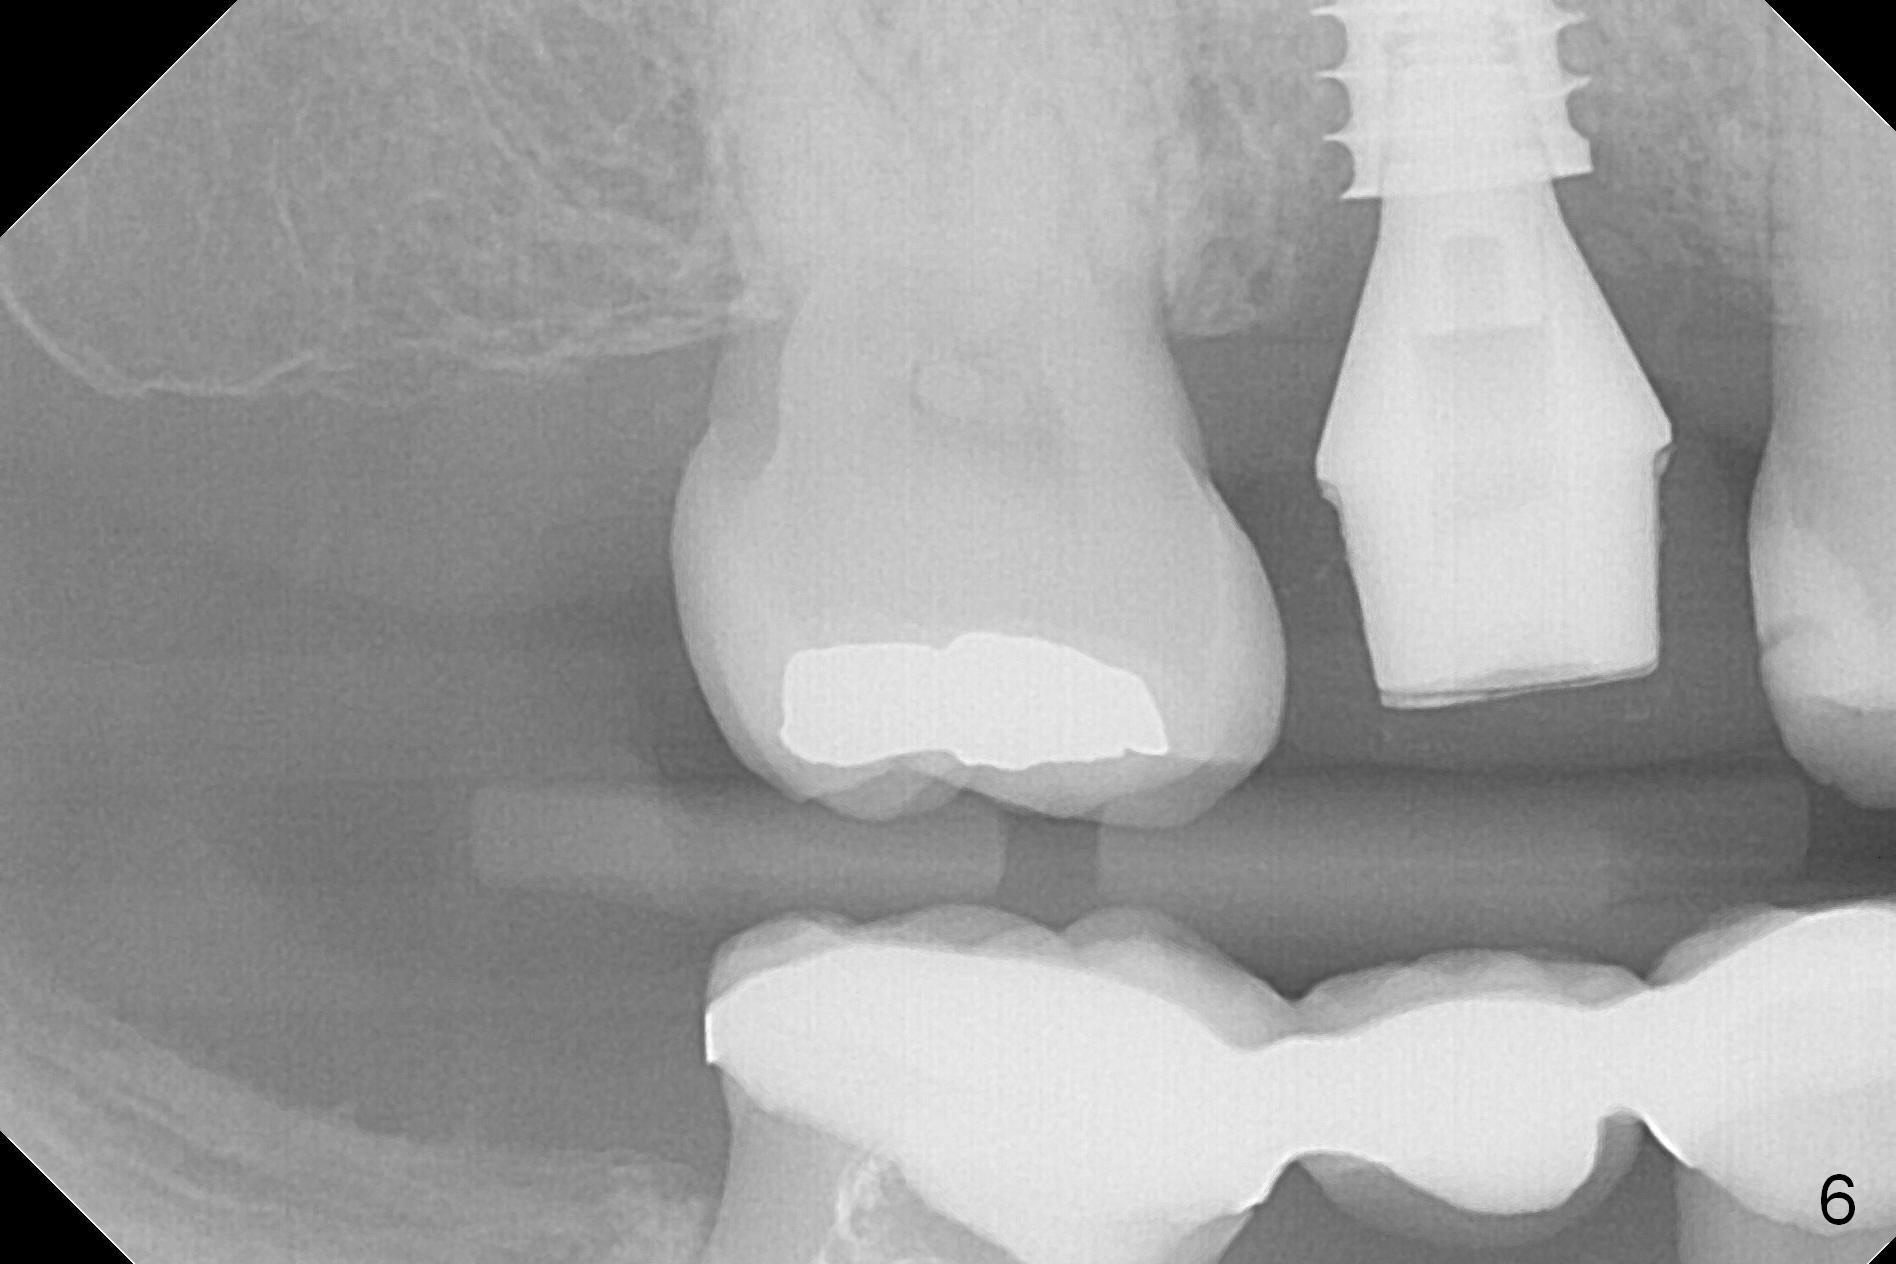

Three weeks postop, the socket has been healing with simultaneous buccal plate collapsing (Fig.5 *, as compared to Fig.2). A larger abutment (7.0-8.5 mm) or a provisional with buccal subgingival margin may decrease the postop shrinking (1,2). There is no bone loss 3 months postop (Fig.6,7). The screw needs to be retightened 9 months post cementation (Fig.8, when the tooth crown is being fabricated at #18). Unilateral mastication is a predisposing factor, since the tooth #19 is missing. When the crown becomes loose again 3 years later, the hex fractures inside the implant. After its removal (Fig.9), a narrower abutment is placed for a new crown (Fig.10: 5x4(4) vs. 6.5x4(4) mm). The implant was placed deep enough without thread exposure; now with apparently complete abutment seating (Fig.11,12). The similar complication may recur due to refusal to have implant at #19 (fear of nerve injury).